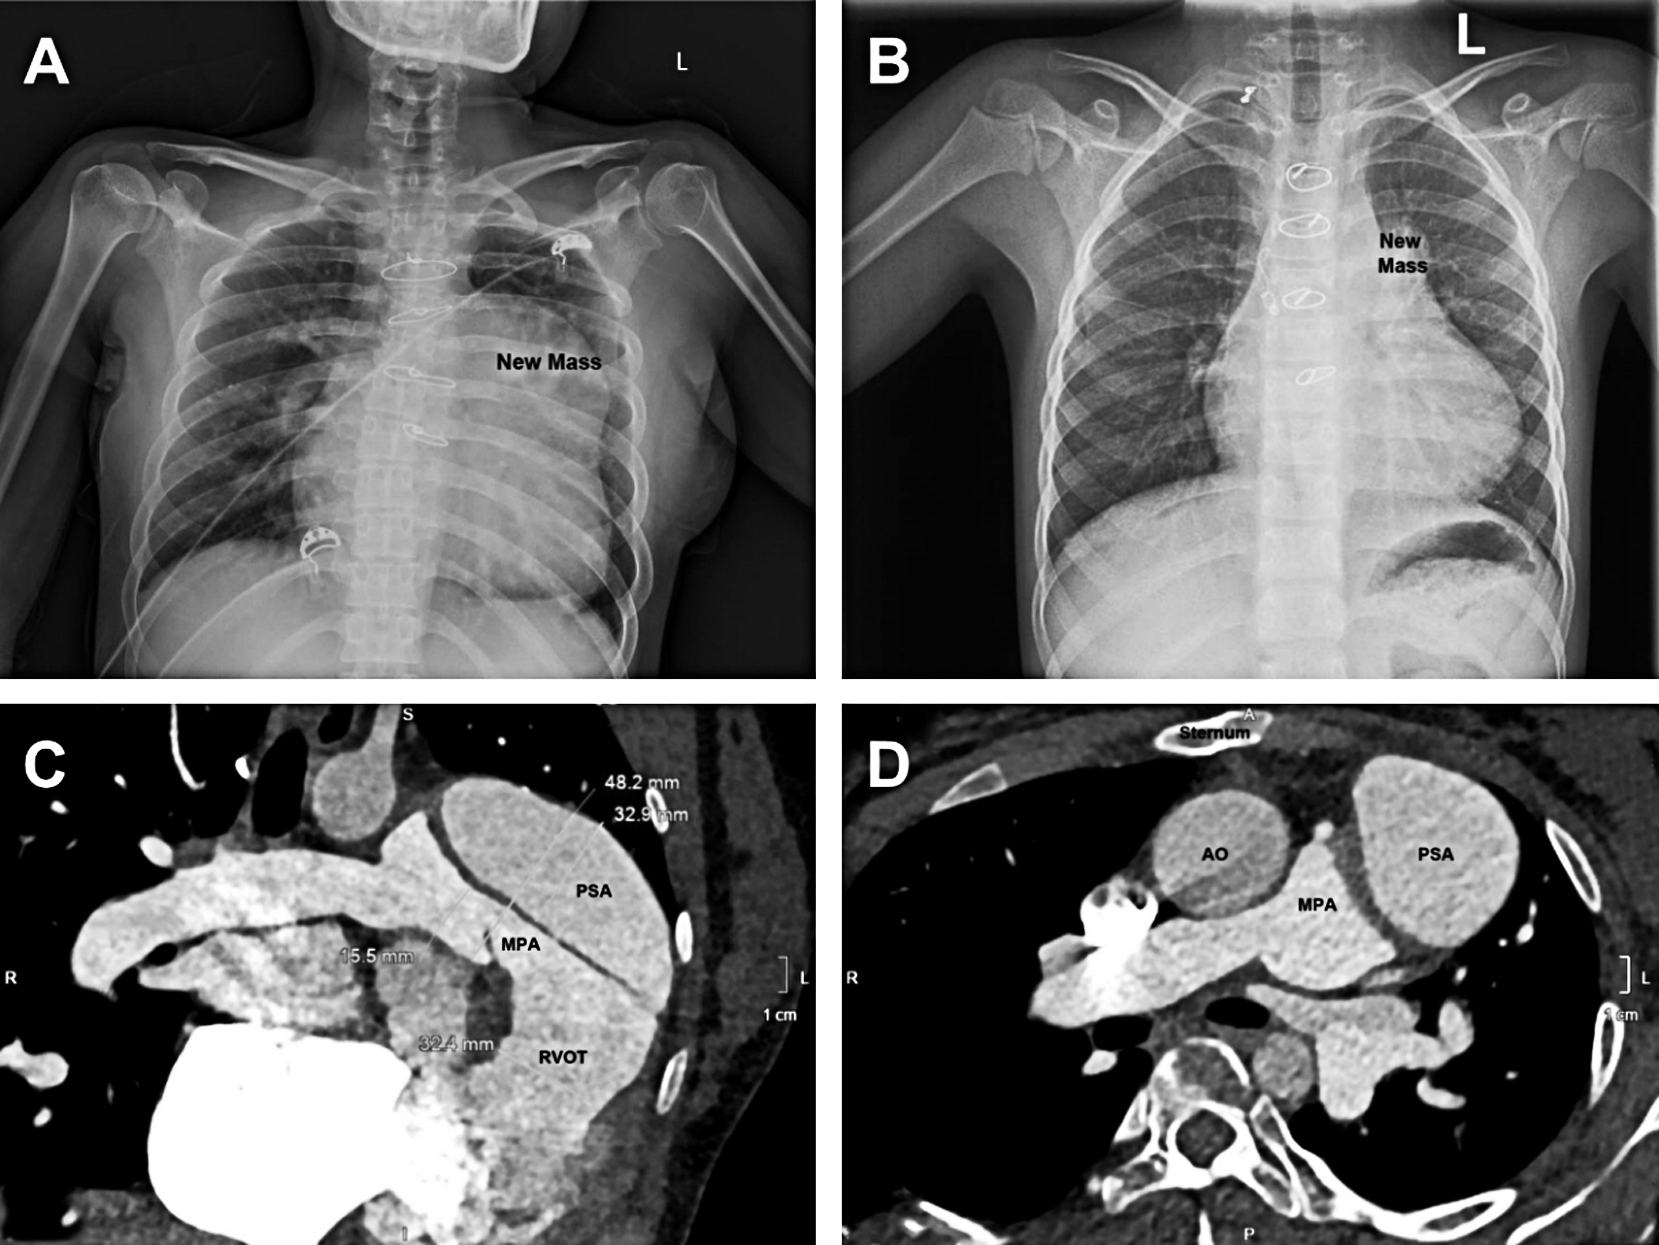

Five patients had a new mass in the left superior mediastinum on chest X ray film (Figs. 1A and 1B), and the other 2 patients had a nearly normal radiograph. The size of aneurysms ranged from 7.6 mm × 7.6 mm to 40 mm × 70 mm. The computed tomography scan showed that the pseudoaneurysm compressed the main pulmonary artery obviously in the patient No. 2 (Fig. 1C). In the patient No. 4 (infection caused pseudoaneurysm), the pseudoaneurysm decreased from 25 mm × 18 mm at the discovery to 7.6 mm × 7.6 mm after treatment with antibiotics for two months. Neither of the pseudoaneurysm sac contained visible thrombus. Although the pseudoaneurysm was detected by echocardiography in most of the patients (6/7), a computed tomography was taken to identify the diagnosis. The echocardiography and computed tomography showed that the pseudoaneurysms were off to the left of the sternum but not in the midline, as indicated in Fig. 1D, therefore, the concern about injury to the pseudoaneurysm and cardiac structures during the sternotomy did not occur.

Figure 1: Radiological feature of pseudoaneurysm. (A) a giant new mass formed in the left superior mediastinum. (B) a small new mass was showed. (C) the giant pseudoaneurysm compressed the main pulmonary artery obviously. (D) the pseudoaneurysms are off to the left of the sternum but not in the midline